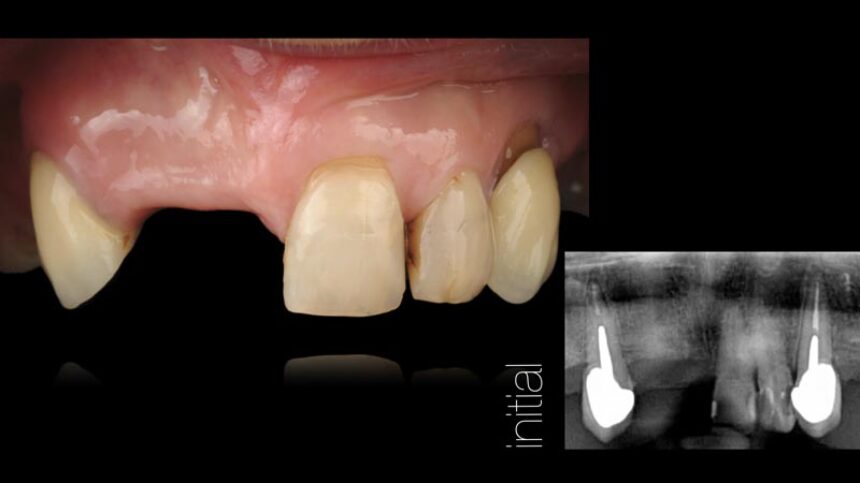

Την διημερίδα θα πλαισιώσει επίσης ο Dr. Iñaki Gamborena εστιάζοντας τις ομιλίες του στους σημαντικούς εκείνους παράγοντες που επηρεάζουν την επιτυχία της θεραπείας στην αισθητική ζώνη τόσο σε ασθενείς με αμιγώς οδοντικό φραγμό, αλλά και εμφυτευματικές αποκαταστάσεις. Οι παρουσιάσεις του θα περιέχουν τη χειρουργική, αλλά και την προσθετική αντιμετώπιση των περιστατικών αυτών και επίσης και αυτός θα επεκταθεί στη διαχείριση πολύπλοκων περιστατικών που έχουν αποτύχει στο παρελθόν.

Αισθητική Οδοντιατρική με Εμφυτεύματα – βασικά επιστημονικά στοιχεία

Ανατομικοί παράγοντες με καθοριστικό ρόλο στην αισθητική αποκατάσταση επί εμφυτευμάτων – Διάγνωση και σχεδιασμός θεραπείας.

Διαχείριση μαλακών ιστών.

Χειρουργικές τεχνικές για την αύξηση των σκληρών και των μαλακών ιστών.